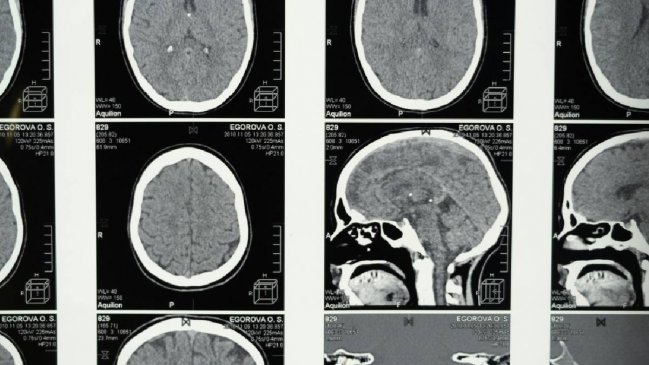

Las mujeres respondieron preguntas sobre temas como el sueño y si sufrían de depresión y ansiedad, mientras que algunas participaron en pruebas cognitivas. Alrededor de 11.000 mujeres también se sometieron a resonancias magnéticas (RM) para que los investigadores pudieran observar la estructura del cerebro.